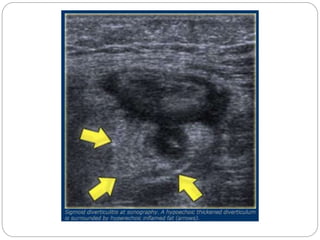

Sigmoid diverticulitis

In diverticulitis sonography and CT show

diverticulosis with segmental colonic wall

thickening and inflammatory changes in the fat

surrounding a diverticulum.

Diverticulitis

A case of diverticulitis showing a thickened sigmoid colon and a diverticulum